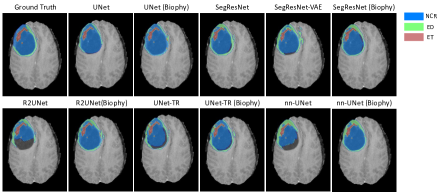

Main Comparison Visualisation in Fig. 3 demonstrates that biophysics-informed regularisation notably enhances tumour segmentation in various networks, yielding results that align more closely with ground truth. This method surpasses traditional dice loss and VAE regularisation by capturing tumour boundaries and structures more effectively, showcasing its potential to improve segmentation across different neural architectures.